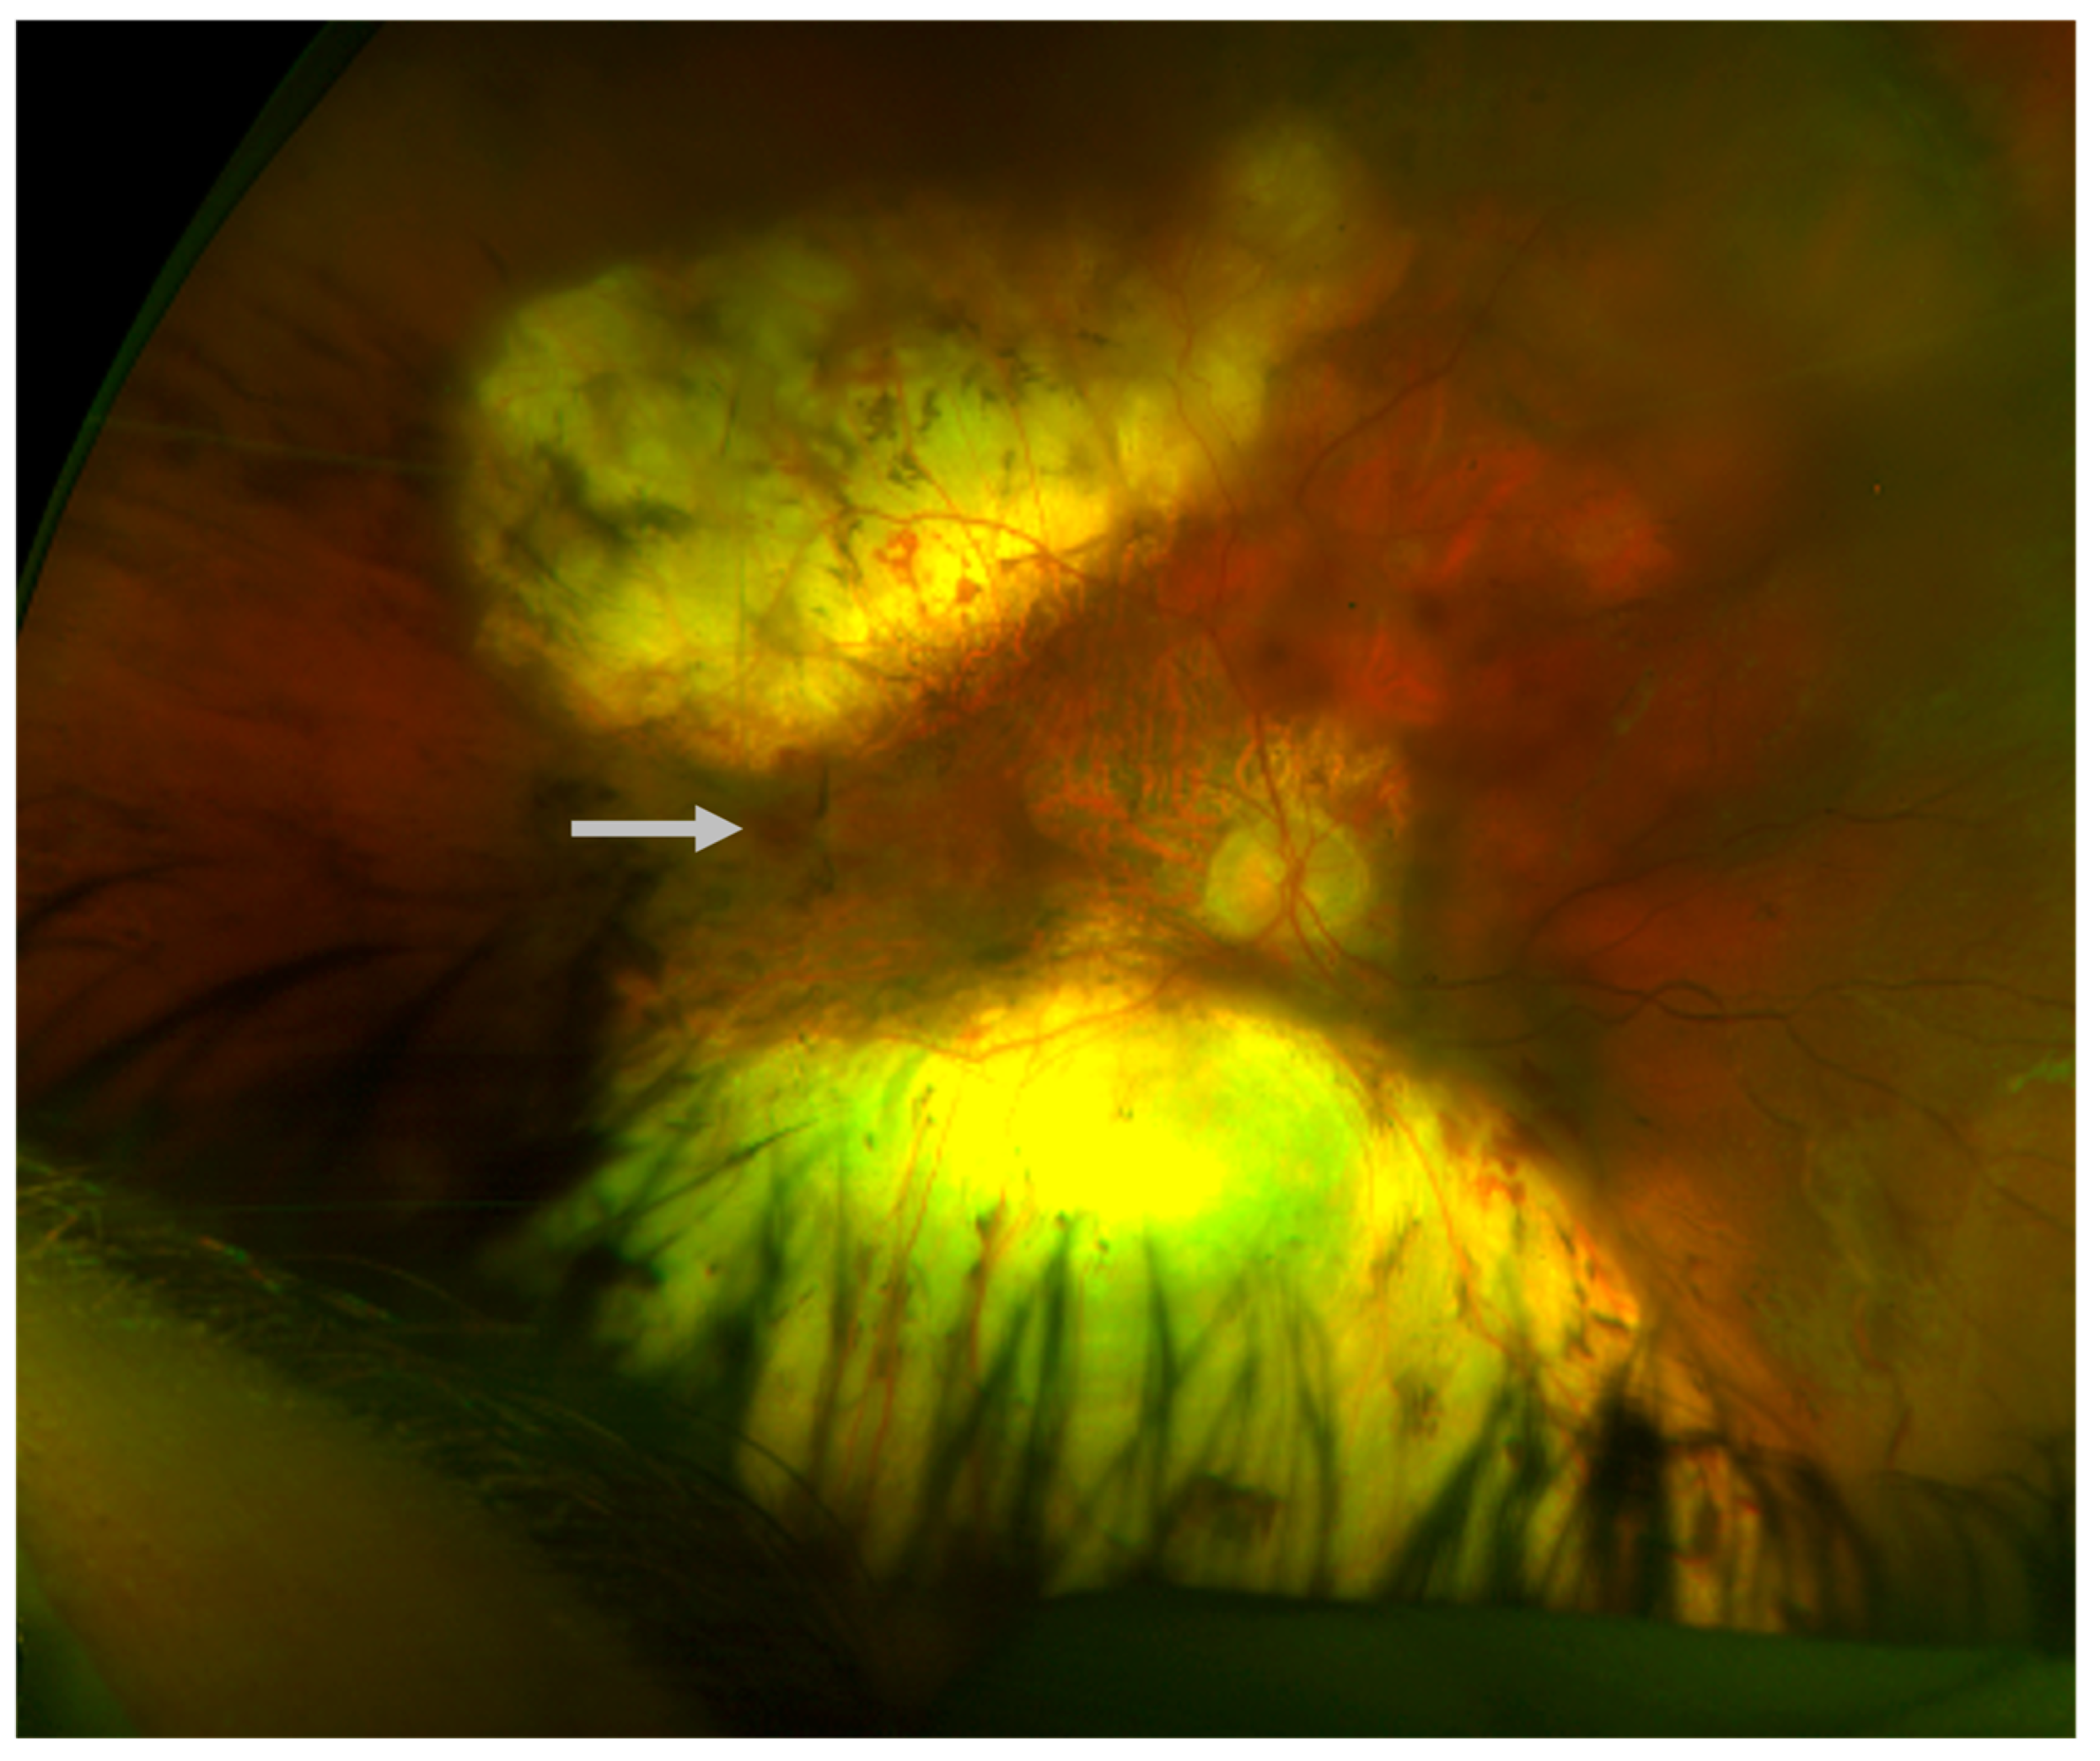

Figure 1.

Chorioretinal atrophy of the right eye; macular view (left) and nasal retina (right), age 10.

An 8-year-old male presented to the pediatric ophthalmology clinic for evaluation of possible strabismus and poor vision. Past medical history was significant for microcephaly- and lymphedema-related developmental delays requiring special education and speech therapy, as well as a history of seizures (in remission without antiepileptic drugs for at least one year). The patient had been clinically diagnosed with microcephaly–lymphedema–chorioretinal dysplasia syndrome (MLCRD) prior to presentation. His height and weight were in the fifth percentile for his age. Family ocular history was positive only for strabismus, and there was a maternal family history of hereditary lymphedema. Upon initial examination, visual acuity was 20/400 eccentrically in the right eye with a correction of −0.50 +1.00 × 180 and 20/60 in the left eye with a correction of −0.50. Visual fields were full to confrontation, and extraocular movements were normal. The anterior segment examination was within normal limits. A dilated fundus exam demonstrated areas of retinal pigment epithelium deposits and chorioretinal atrophy (CRA) bilaterally (Figure 1 and Figure 2).